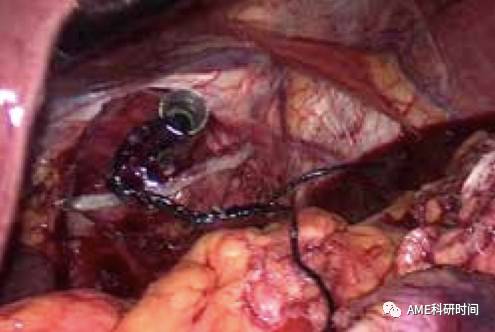

4反式抵钉座置入法(HDST法,反穿刺法):腹腔外,用2-0肠线穿过穿刺头打结10余个,保留针。同侧方置入法置入钉钻头及打开食管,钉座光滑面朝上,完全置入食管内(如图15),将针线距开口近端0.5 cm处缝穿出食管(如图16), 由肠线引出穿刺头,直线切割闭合器紧贴穿刺头闭合断离食管,从食管前壁引出钉钻头,取下穿刺头(如图17-18)。

图15 抵入钉钻头

图16 缝穿出中心杆

图17 牵拉出中心杆

图18 取出穿刺头